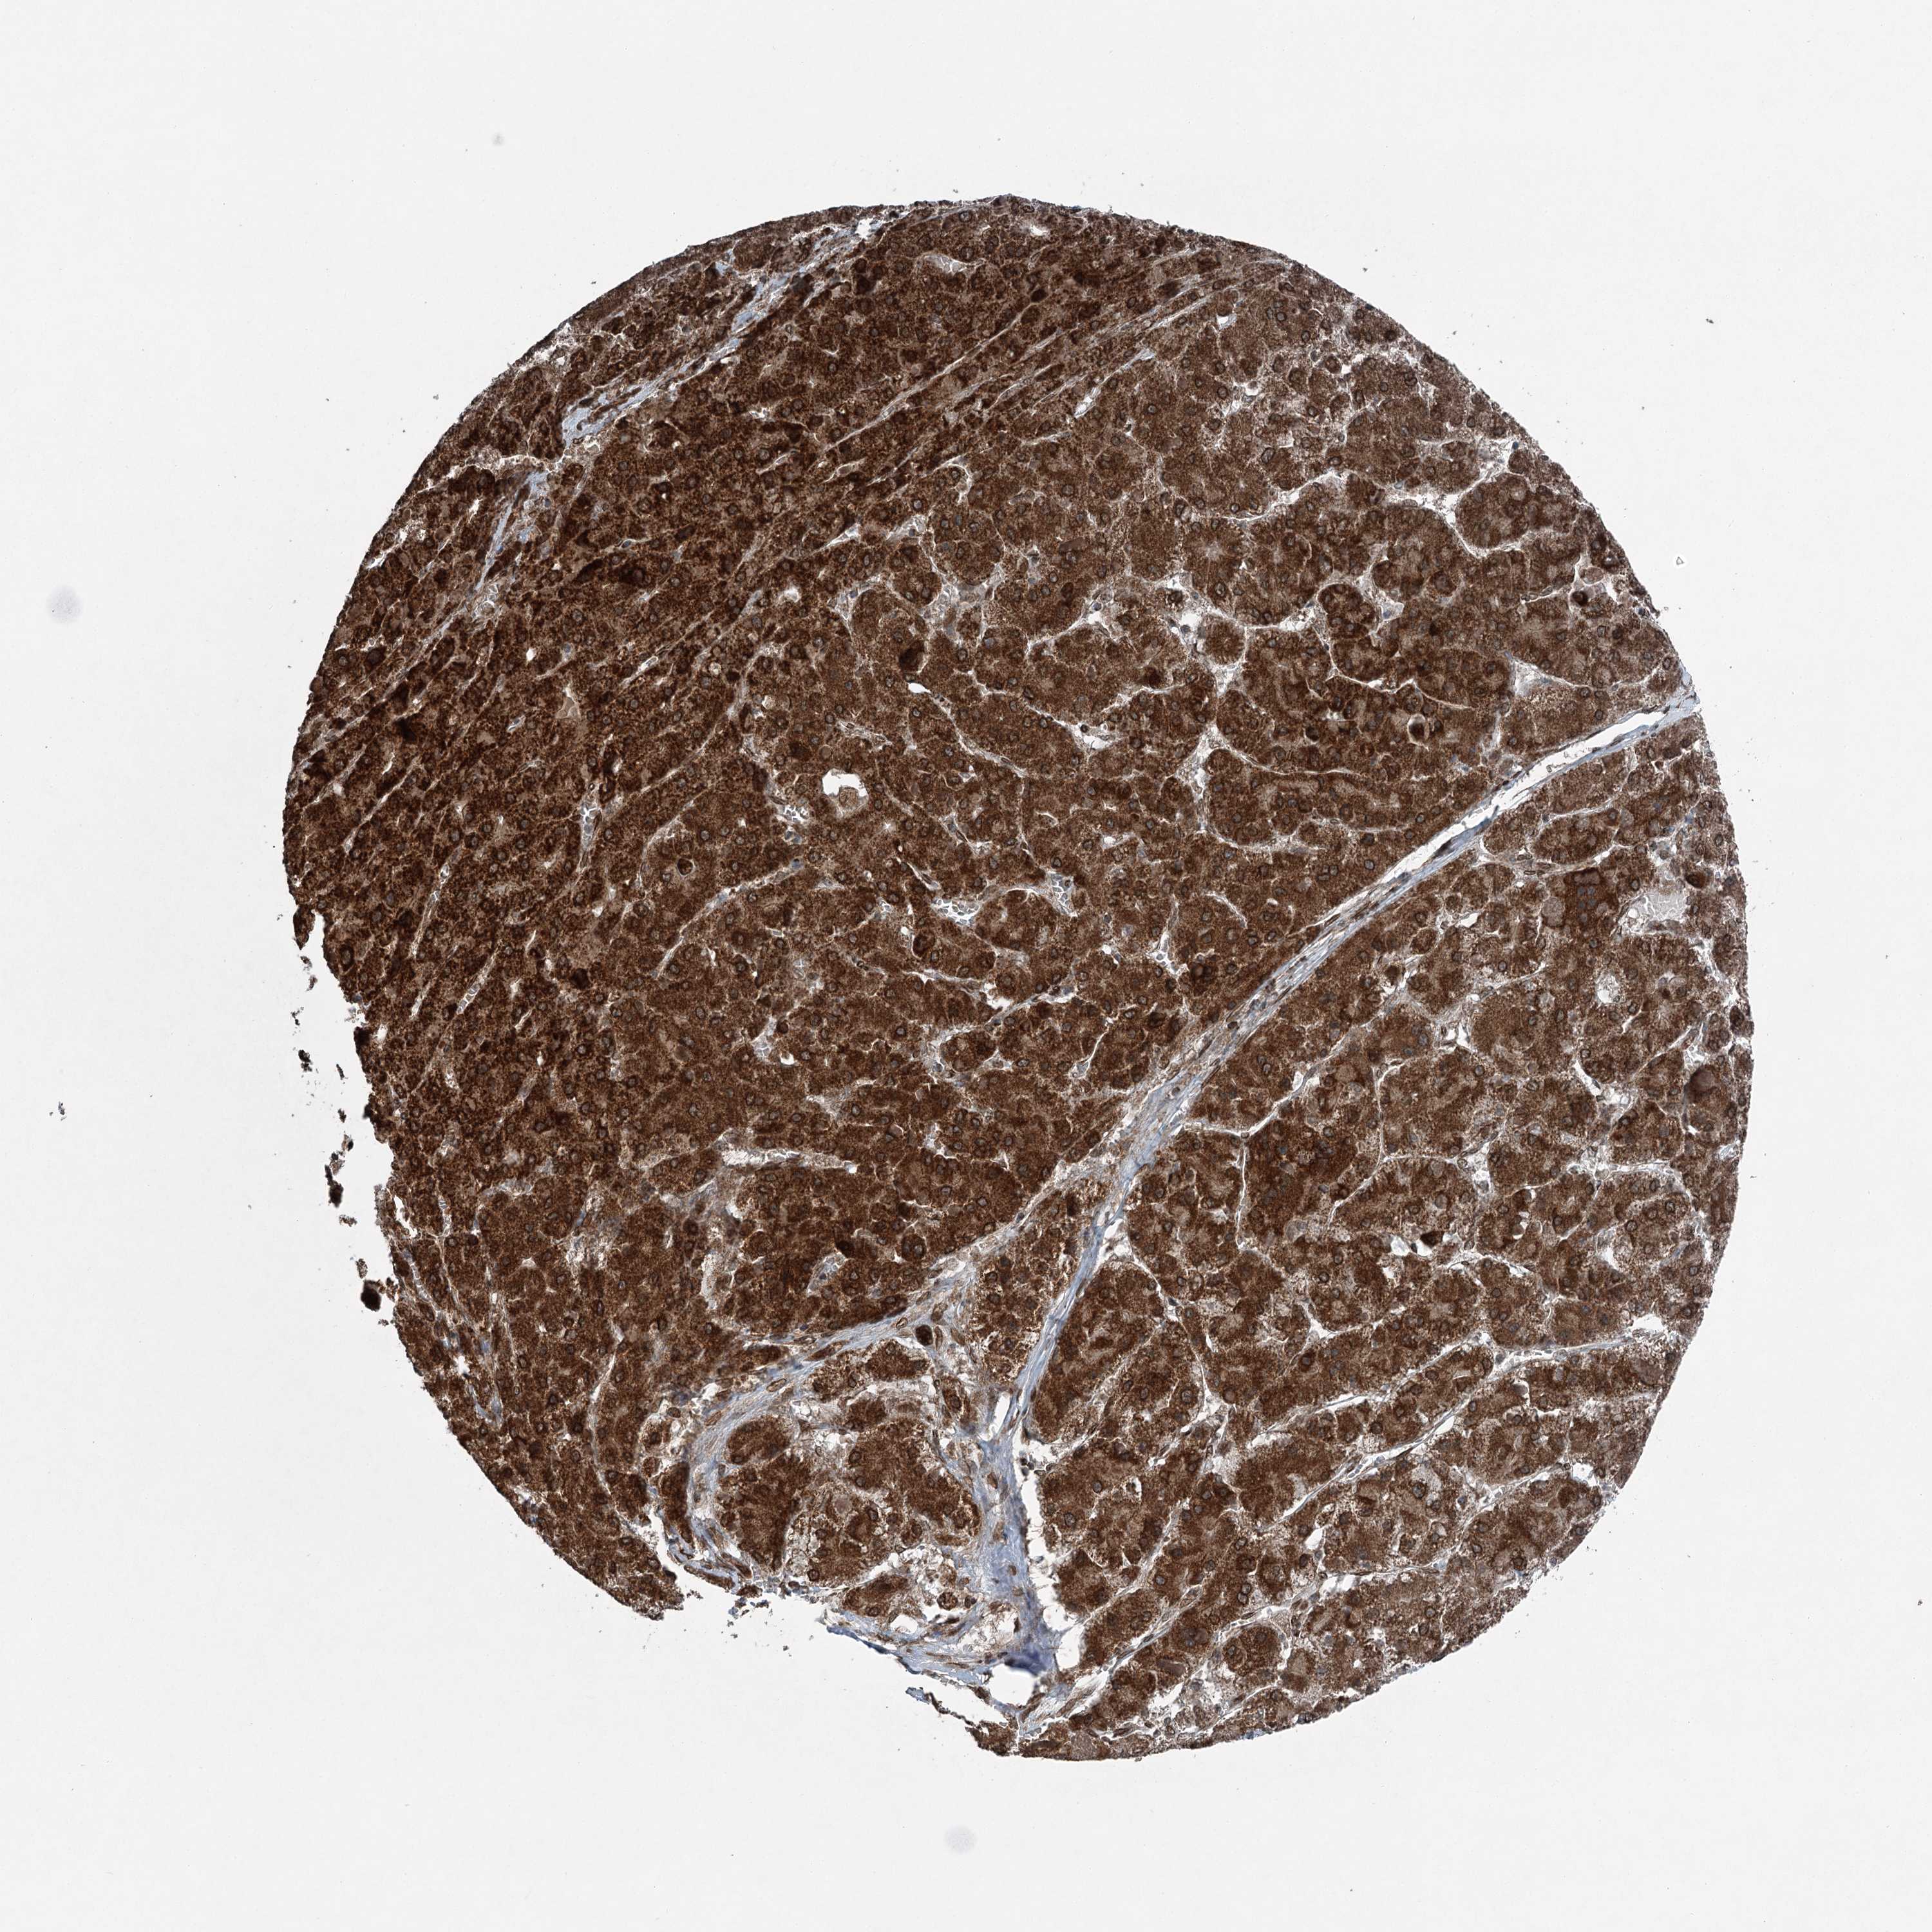

LIVER CANCER - Protein expressioni

A mouse-over function shows sample information and annotation data. Click on an image to view it in a full screen mode. Samples can be filtered based on level of antibody staining by selecting one or several of the following categories: high, medium, low and not detected. The assay and annotation is described here.

Note that samples used for immunohistochemistry by the Human Protein Atlas do not correspond to samples in the TCGA dataset.

Antibody stainingi

Antibody staining in the annotated cell types in the current human tissue is reported as not detected, low, medium, or high, based on conventional immunohistochemistry profiling in selected tissues. This score is based on the combination of the staining intensity and fraction of stained cells.

Each image is clickable and will lead to virtual microscopy that enables deeper exploration of all samples and also displays staining intensity scores, fraction scores and subcellular localization as well as patient and tissue information for each sample.

Antibody HPA036640

Staining

High

Medium

Low

Not detected

Intensity

Strong

Moderate

Weak

Negative

Quantity

>75%

75%-25%

<25%

None

Location

Nuclear

Cytoplasmic/membranous

Cytoplasmic/membranous,nuclear

Cholangiocarcinoma

Carcinoma, Hepatocellular, NOS